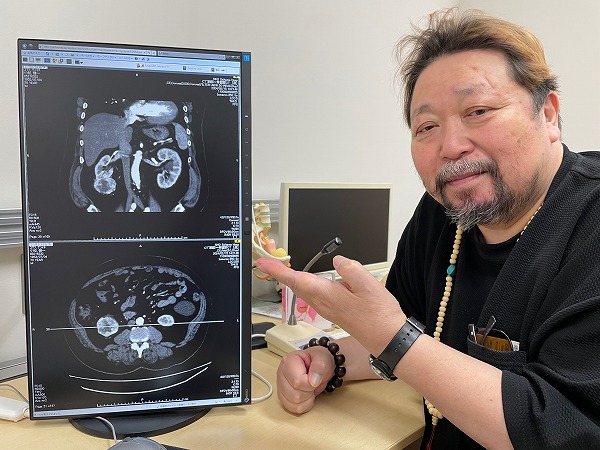

この間、埼玉病院での検査は繰り返された。この映像は1度目の造影剤を入れたCT検査の僕の腎臓の画像。上の画像の左部分の腎臓の下に丸く付いているのが癌の腫瘍。この時点で直径7センチ大だった。下の画像は輪切りにして見ているもの。やはり左部分の丸いものが腎臓がんである。僕が「腎臓よりも大きく見えますね」と言うとまだ40代と思われる執刀を担当する医師は「そうですね、でもまだ転移は見られませんので早く切りましょう」と言って笑った。この写真はその医師が撮影してくれたもの。僕が写真家であり記録として残したいという希望に沿ってくれたのである。

左がわの丸いのが癌の病巣。

左側の腎臓の下にぶら下がる丸いものが癌の腫瘍。